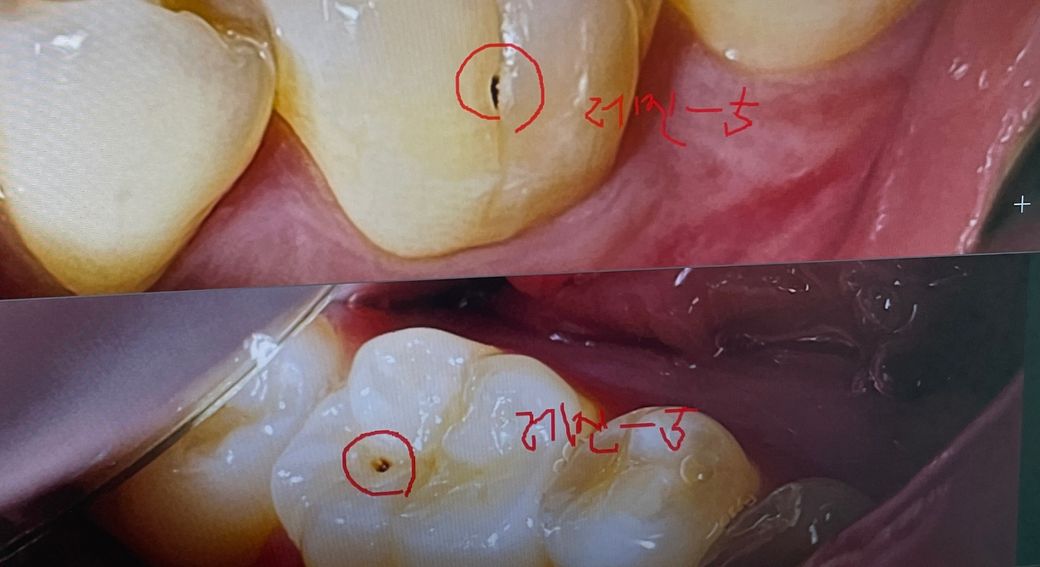

충치 레진 치료 언제가 좋을까요???

충치가 조금 있어서, 원장쌤께서 레진으로 떼워야할 것 같다고 하시는데요. 생활에는 불편함이 없는데 바로 떼우는게 좋을까요? 좀 냅둬도 될까요..

• 1번 째 사진

사진에 보이는 충친는 진행되고 잇는 충치같아서 간단히 충치를 제거하고 레진으로 떼우시는게 좋을것같습니다.

사진으로 보이는 충치는 치아 표면에 구멍이 나있으며 시간이 지나면서 안쪽으로 진행되어 가는 충치로 보입니다.

시간이 지나면 내부로 충치가 더 진행될수 있기때문에 가능하면 빠르게 치료하는것이 좋을것으로 생각됩니다.

큰 충치는 아니나 구멍으로 음식물이 껴서 잘 안빠지면 그게 충치를 더 크게 만들기 때문에 치료해줘도 좋을 단계입니다